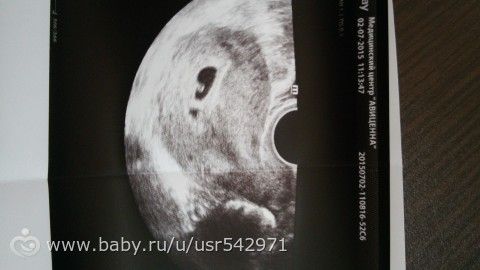

Сегодня первое узи, по месячным 5 недель 4 дня, по овуляции 4 недели 6 дней. Плодное яйцо 5-6мм, мне кажется или на фото виднеется мешочек и эмбрион? Я просто не знаю как должно выглядеть, узист сказал, что мерить пока нечего :)

мешочек есть, а эмбриончик либо по центру черточка, либо в уголочке… фик поймешь))

Мерять и правда пока нечего. Видно очаги повышенной эхогенности, это скорее всего и будет плодное яйцо, но очень мало для точного утверждения.

В смысле? Черное — это и есть плодное яйцо, оно 5-6мм)

Ох, не так выразилась. Одной рукой пишу, другой ужин готовлю пока деть спит )))) в смысле очаги эхогенности в плодном яйце, это скорее всего и есть будущий эмбрион, но пока он максимум шарик немного вытянутой формы.

по серединке виднеется что то